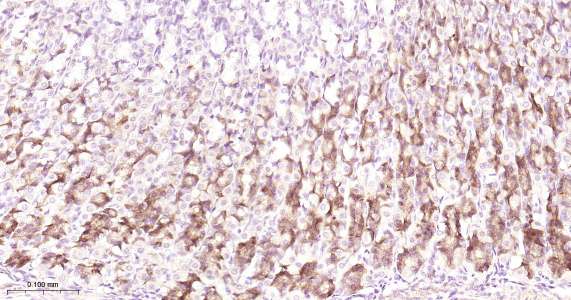

Immunohistochemical analysis of paraffin embedded mouse stomach tissue slide using IHC0463 (AGR2 IHC Kit).

Immunohistochemical analysis of paraffin embedded human small intestine tissue slide using IHC0463 (AGR2 IHC Kit).

Immunohistochemical analysis of paraffin embedded human stomach tissue slide using IHC0463 (AGR2 IHC Kit).

Immunohistochemical analysis of paraffin embedded rat stomach tissue slide using IHC0463 (AGR2 IHC Kit).